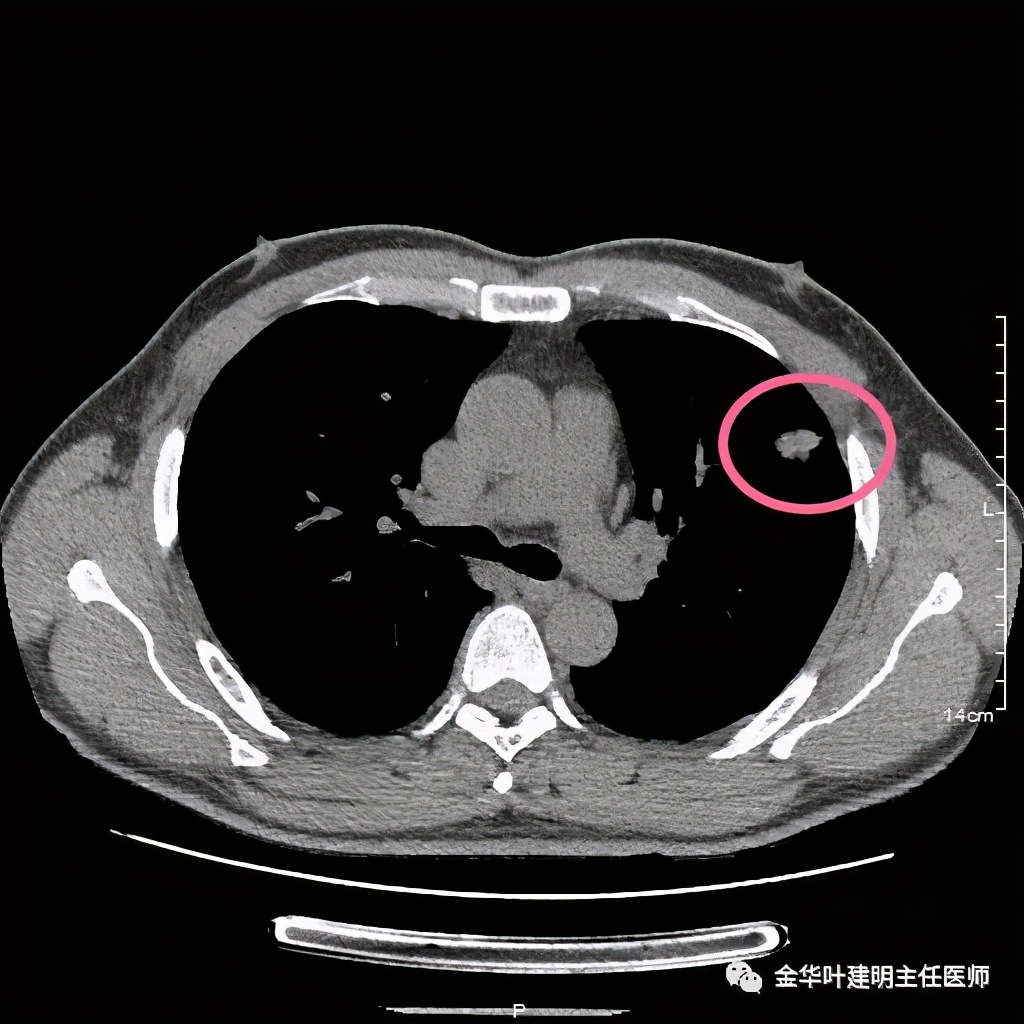

医生告诉患者可以穿刺活检,也可予以胸腔镜下楔形切除。患者方选择手术切除。术后病理示:隐球菌感染伴肉芽肿性炎!

我们来看以往的隐球菌感染是怎样的影像表现:

我们看到它们的共同特征是:实性结节伴有晕征(边缘略糊,看不清的感觉),同时实性的病灶缺乏收缩力(没有胸膜凹陷及毛刺牵拉或纠集感)。